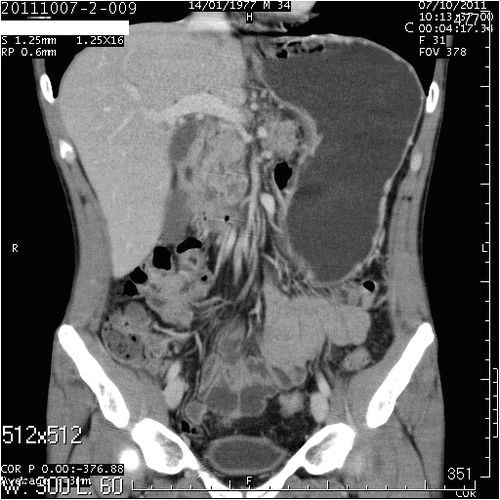

- Комп'ютерна томографія. Це один з найсучасніших методів дослідження, який дозволив практично забути інвазивні методи дослідження. Після комп'ютерної томографії лікар отримує вичерпну інформацію про захворювання після того як ознайомиться з тривимірною моделлю ураженої ділянки тіла,